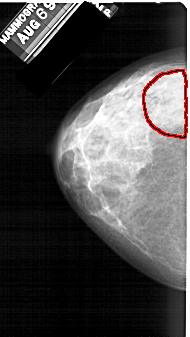

A_1391_1.LEFT_CC

LEFT_CC LINES 5041 PIXELS_PER_LINE 2836 BITS_PER_PIXEL 12 RESOLUTION 43.5 OVERLAY

FILE: A_1391_1.LEFT_CC.OVERLAY

TOTAL_ABNORMALITIES 1

ABNORMALITY 1

LESION_TYPE CALCIFICATION TYPE PLEOMORPHIC DISTRIBUTION SEGMENTAL

ASSESSMENT 4

SUBTLETY 4

PATHOLOGY BENIGN

TOTAL_OUTLINES 1

BOUNDARY